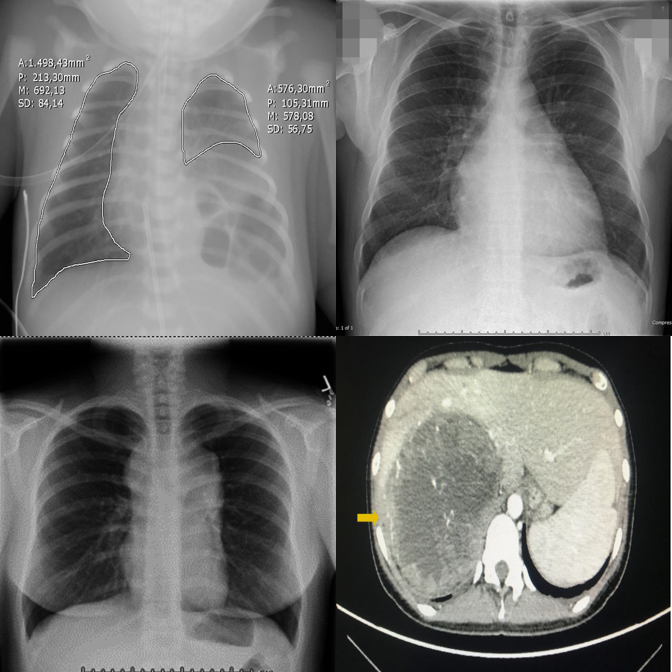

When pointed directly at the outlier, the model can confirm differing modality.

Fails to recognize the modality difference even when the outlier is highlighted.

Medical VLM incorrectly denies an obvious modality mismatch.

Hallucinates an anomaly in the highlighted panel despite it being consistent.

"Always-find-something" bias is triggered by the red box visual cue.

Best negative control accuracy among medical VLMs — capable of restraint.

Dense 3×3 grids make it harder to compare even when the outlier is highlighted.

Smaller proprietary models struggle with visual referring on larger grids.

Even the latest reasoning models fail on 3×3 visual referring tasks.

Incorrectly flags a perfectly consistent 3×3 negative control as an outlier.

Hallucinates a detailed physical abnormality despite the uniform grid.

Shows strong "always-find-something" bias triggered by the bounding box.

Fabricates a difference in a perfectly consistent 3×3 grid.

Generates plausible-sounding but entirely fabricated clinical reasoning.

One of few models capable of correctly suppressing false alarms on 3×3 grids.

Proprietary models perform best on visual referring with clear anatomy differences.

Cross-anatomy mismatches are well handled when the panel is directly highlighted.